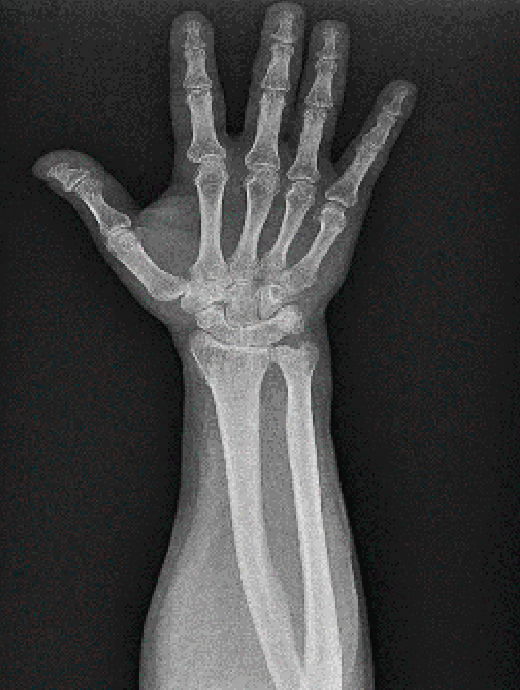

Figura 1. Radiografía de muñeca. Proyección anteroposterior.

Se solicitan estudios de imagen. En primer lugar, rayos X de muñeca en proyección anteroposterior (AP) (Figura 1), en los que se evidencia un aumento del espacio cubital y presencia de la fusión lunopiramidal. Se coloca una inmovilización con muñequera elástica. Se solicita (Figura 2) tomografía axial computarizada (TAC) para la confirmación del diagnóstico y resonancia magnética (RM) (Figura 3) de mano para valorar las estructuras blandas. Los hallazgos de la TAC reportan la coalición lunopiramidal de tipo Minnaar III y la RM realizada para valorar lesiones asociadas de partes blandas reporta sinovitis. El resto de los elementos no muestran alteraciones.